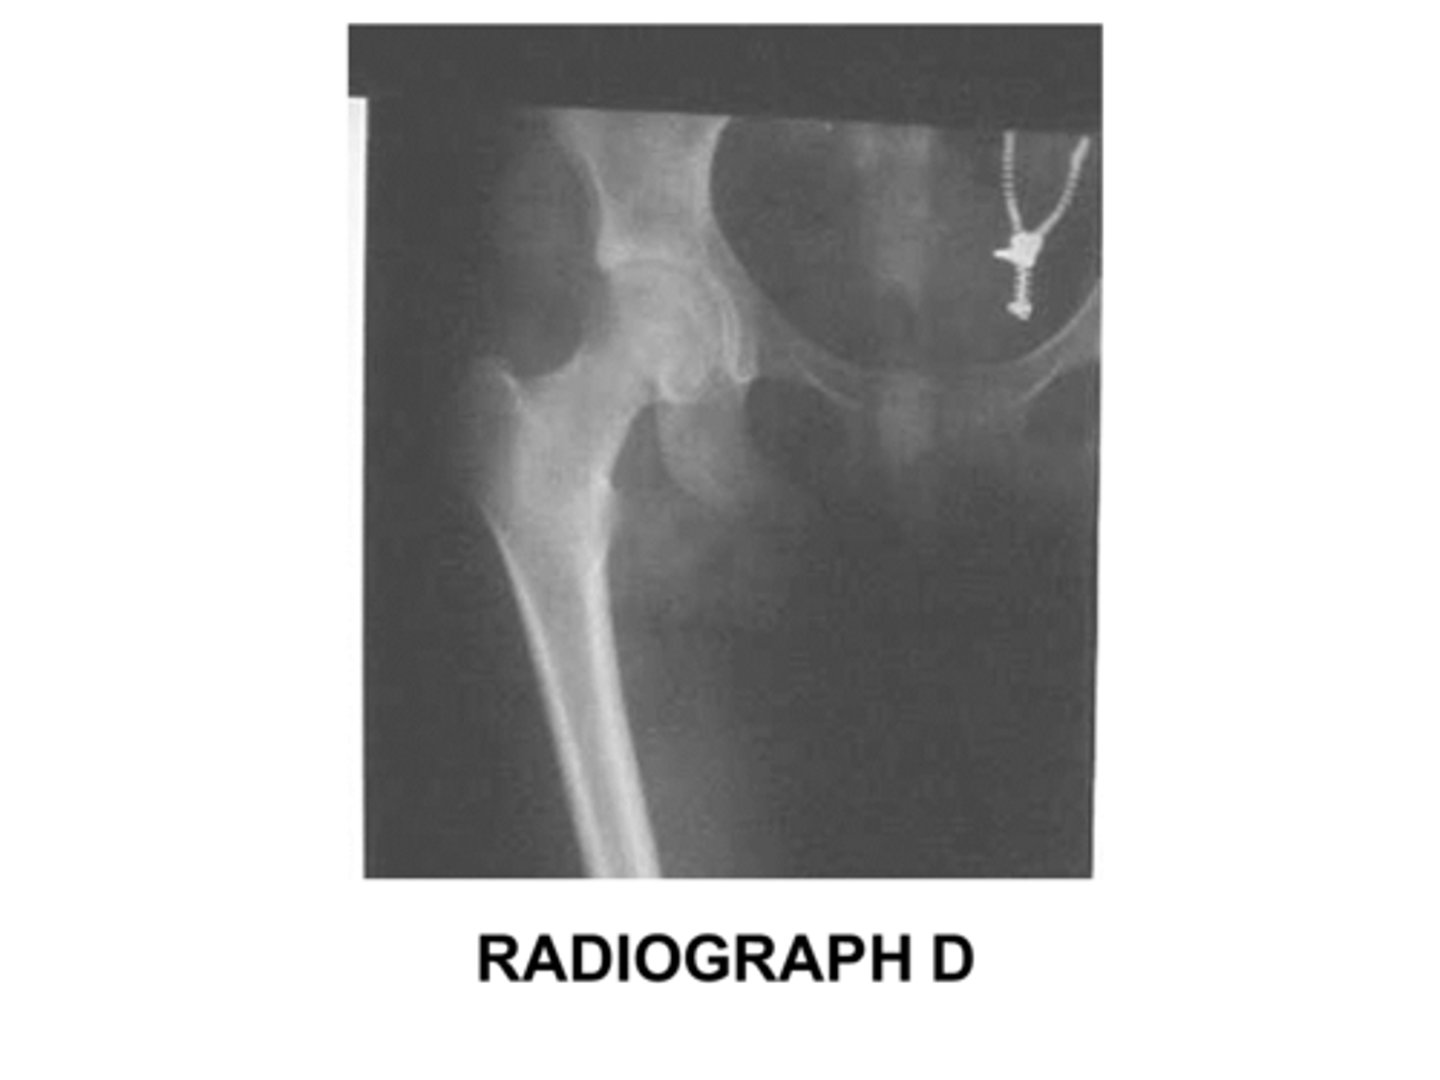

Identify the projection:

AP Hip

Axiolateral Hip (Danelius-Miller)

AP oblique hip (Modified Cleaves)

Lateral hip (Lauenstein)

AP oblique hip

Lateral hip

Axiolateral hip